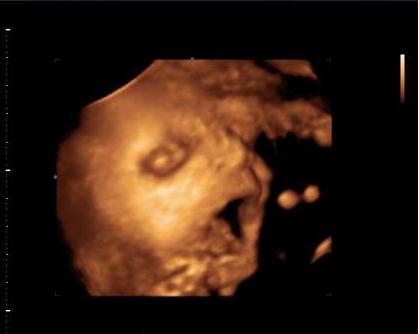

Dalma tegnap az uh-n megmutatta milyen rendes csaj.. Befordult irányba

kaptunk ajándék képet:

Kép